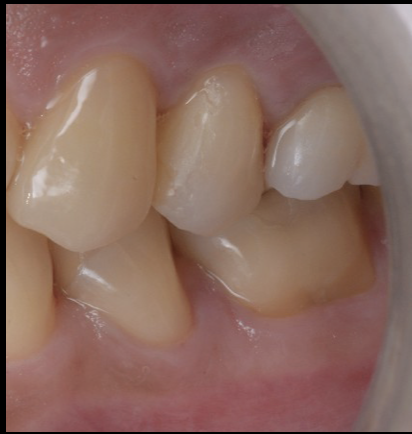

治療後の状態

治療後には、以下のような改善が見られました。

・ 痛み・腫れの消失

・ レントゲンで透過像が縮小し骨の回復

・ 歯肉が自然で健康的なラインに

・ セラミッククラウンが自然に適合

・ 咬合が安定し噛みやすくなる

外科なしでここまで改善できるのは、

根管治療・補綴・咬合の3つを総合的に設計しているからこそ です。